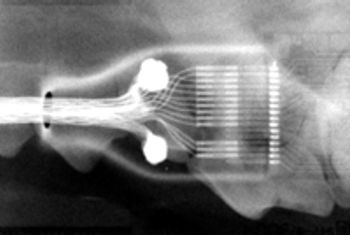

Intraoral radiographs are essential to perform quality dental therapy. Teeth can be cleaned and polished without seeing radiographic images below the gingiva, but "dentistry" cannot be performed properly.

All small animal practitioners routinely take radiographs of patients where indicated. Radiographs simply put, help the veterinarian evaluate the patient.